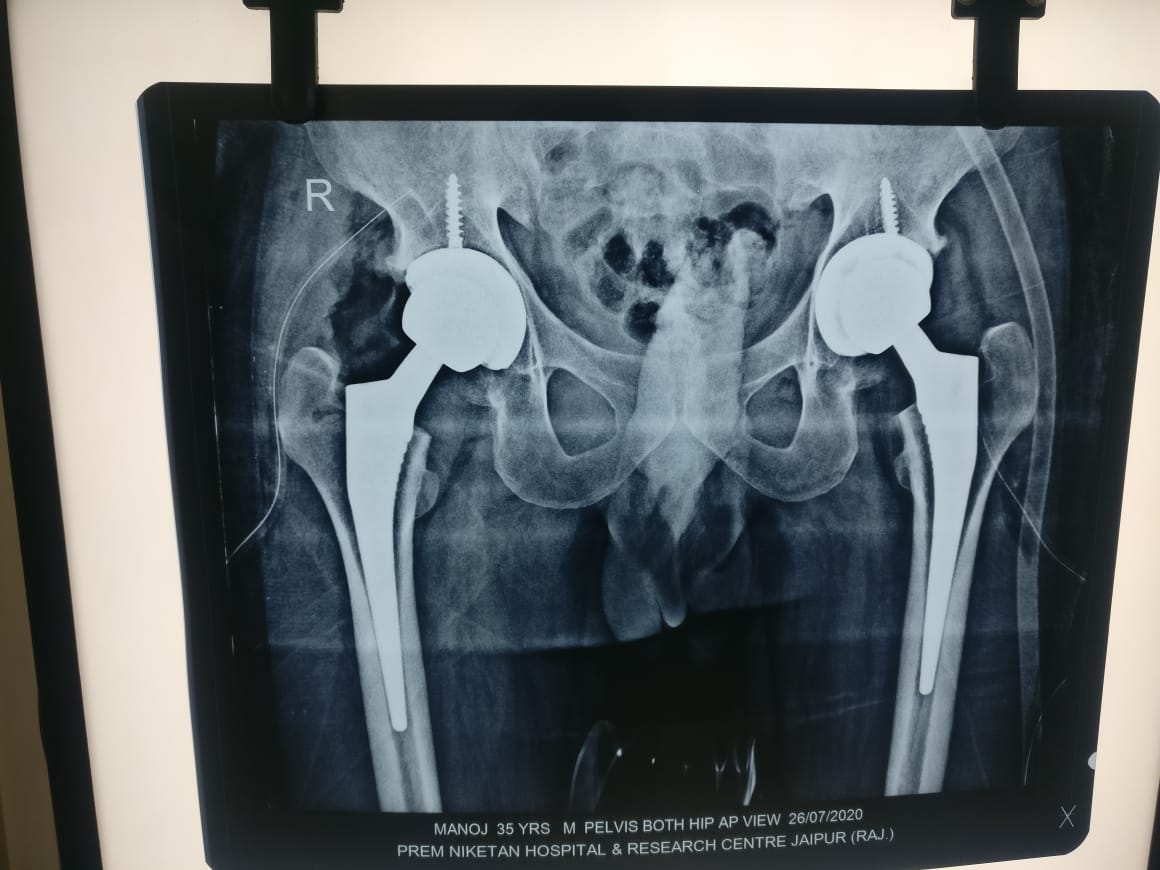

THR done for AVN

Total Hip replacement

Uncemented thr